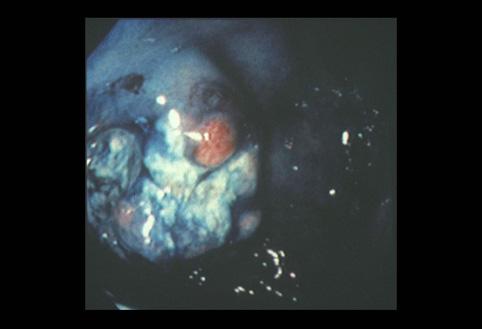

疾患(病理主体)の分類悪性上皮性腫瘍/その他

部位(臓器別)胃(部位)/噴門

検査方法内視鏡

腫瘍の肉眼分類1型(腫瘤型)/

病変の最大径(ミリ)40以上

腫瘍の深達度s(a)